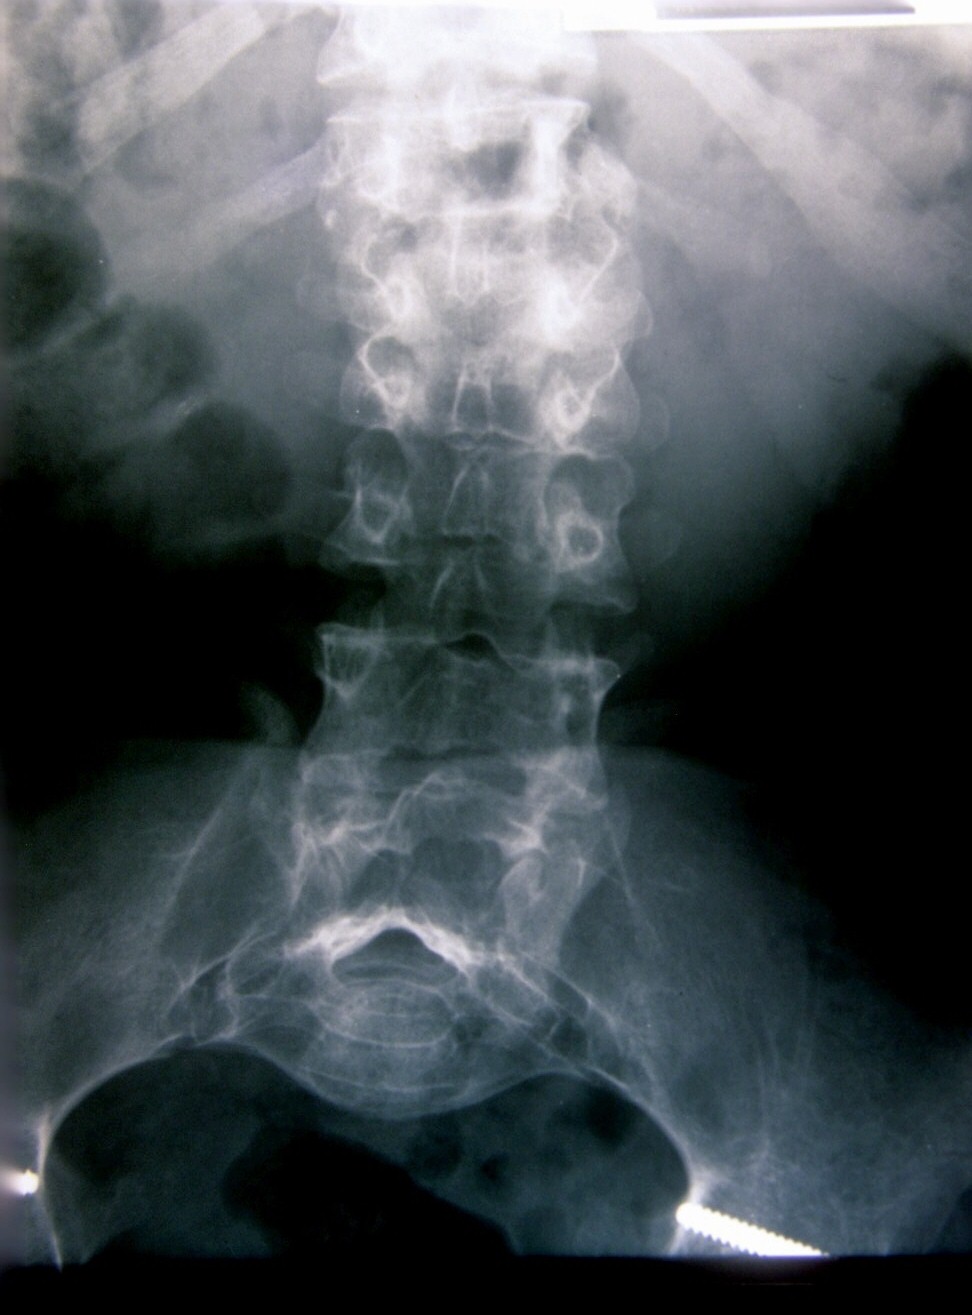

Seudoacondroplasia. [Pseudoachondroplasia]